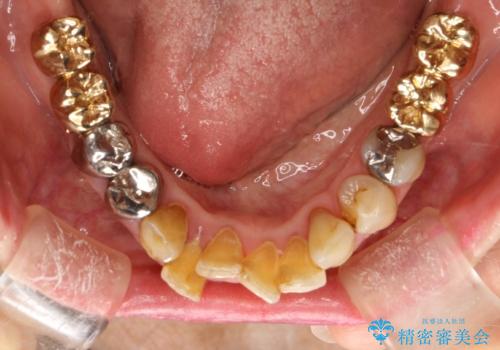

片顎の部分矯正 ワイヤーを用いて短期間でガタつきを改善する

- 歯列から逸脱した歯を1本抜歯し、ワイヤーを用いて短期間で歯列をきれいに整えた。

下顎の歯列を整えることで、上の歯に対して無理な咬み合わせで強い負担がかかることもなくなり、また歯ブラシもしやすくなることで、長期的に良い環境を整えることにつながります。